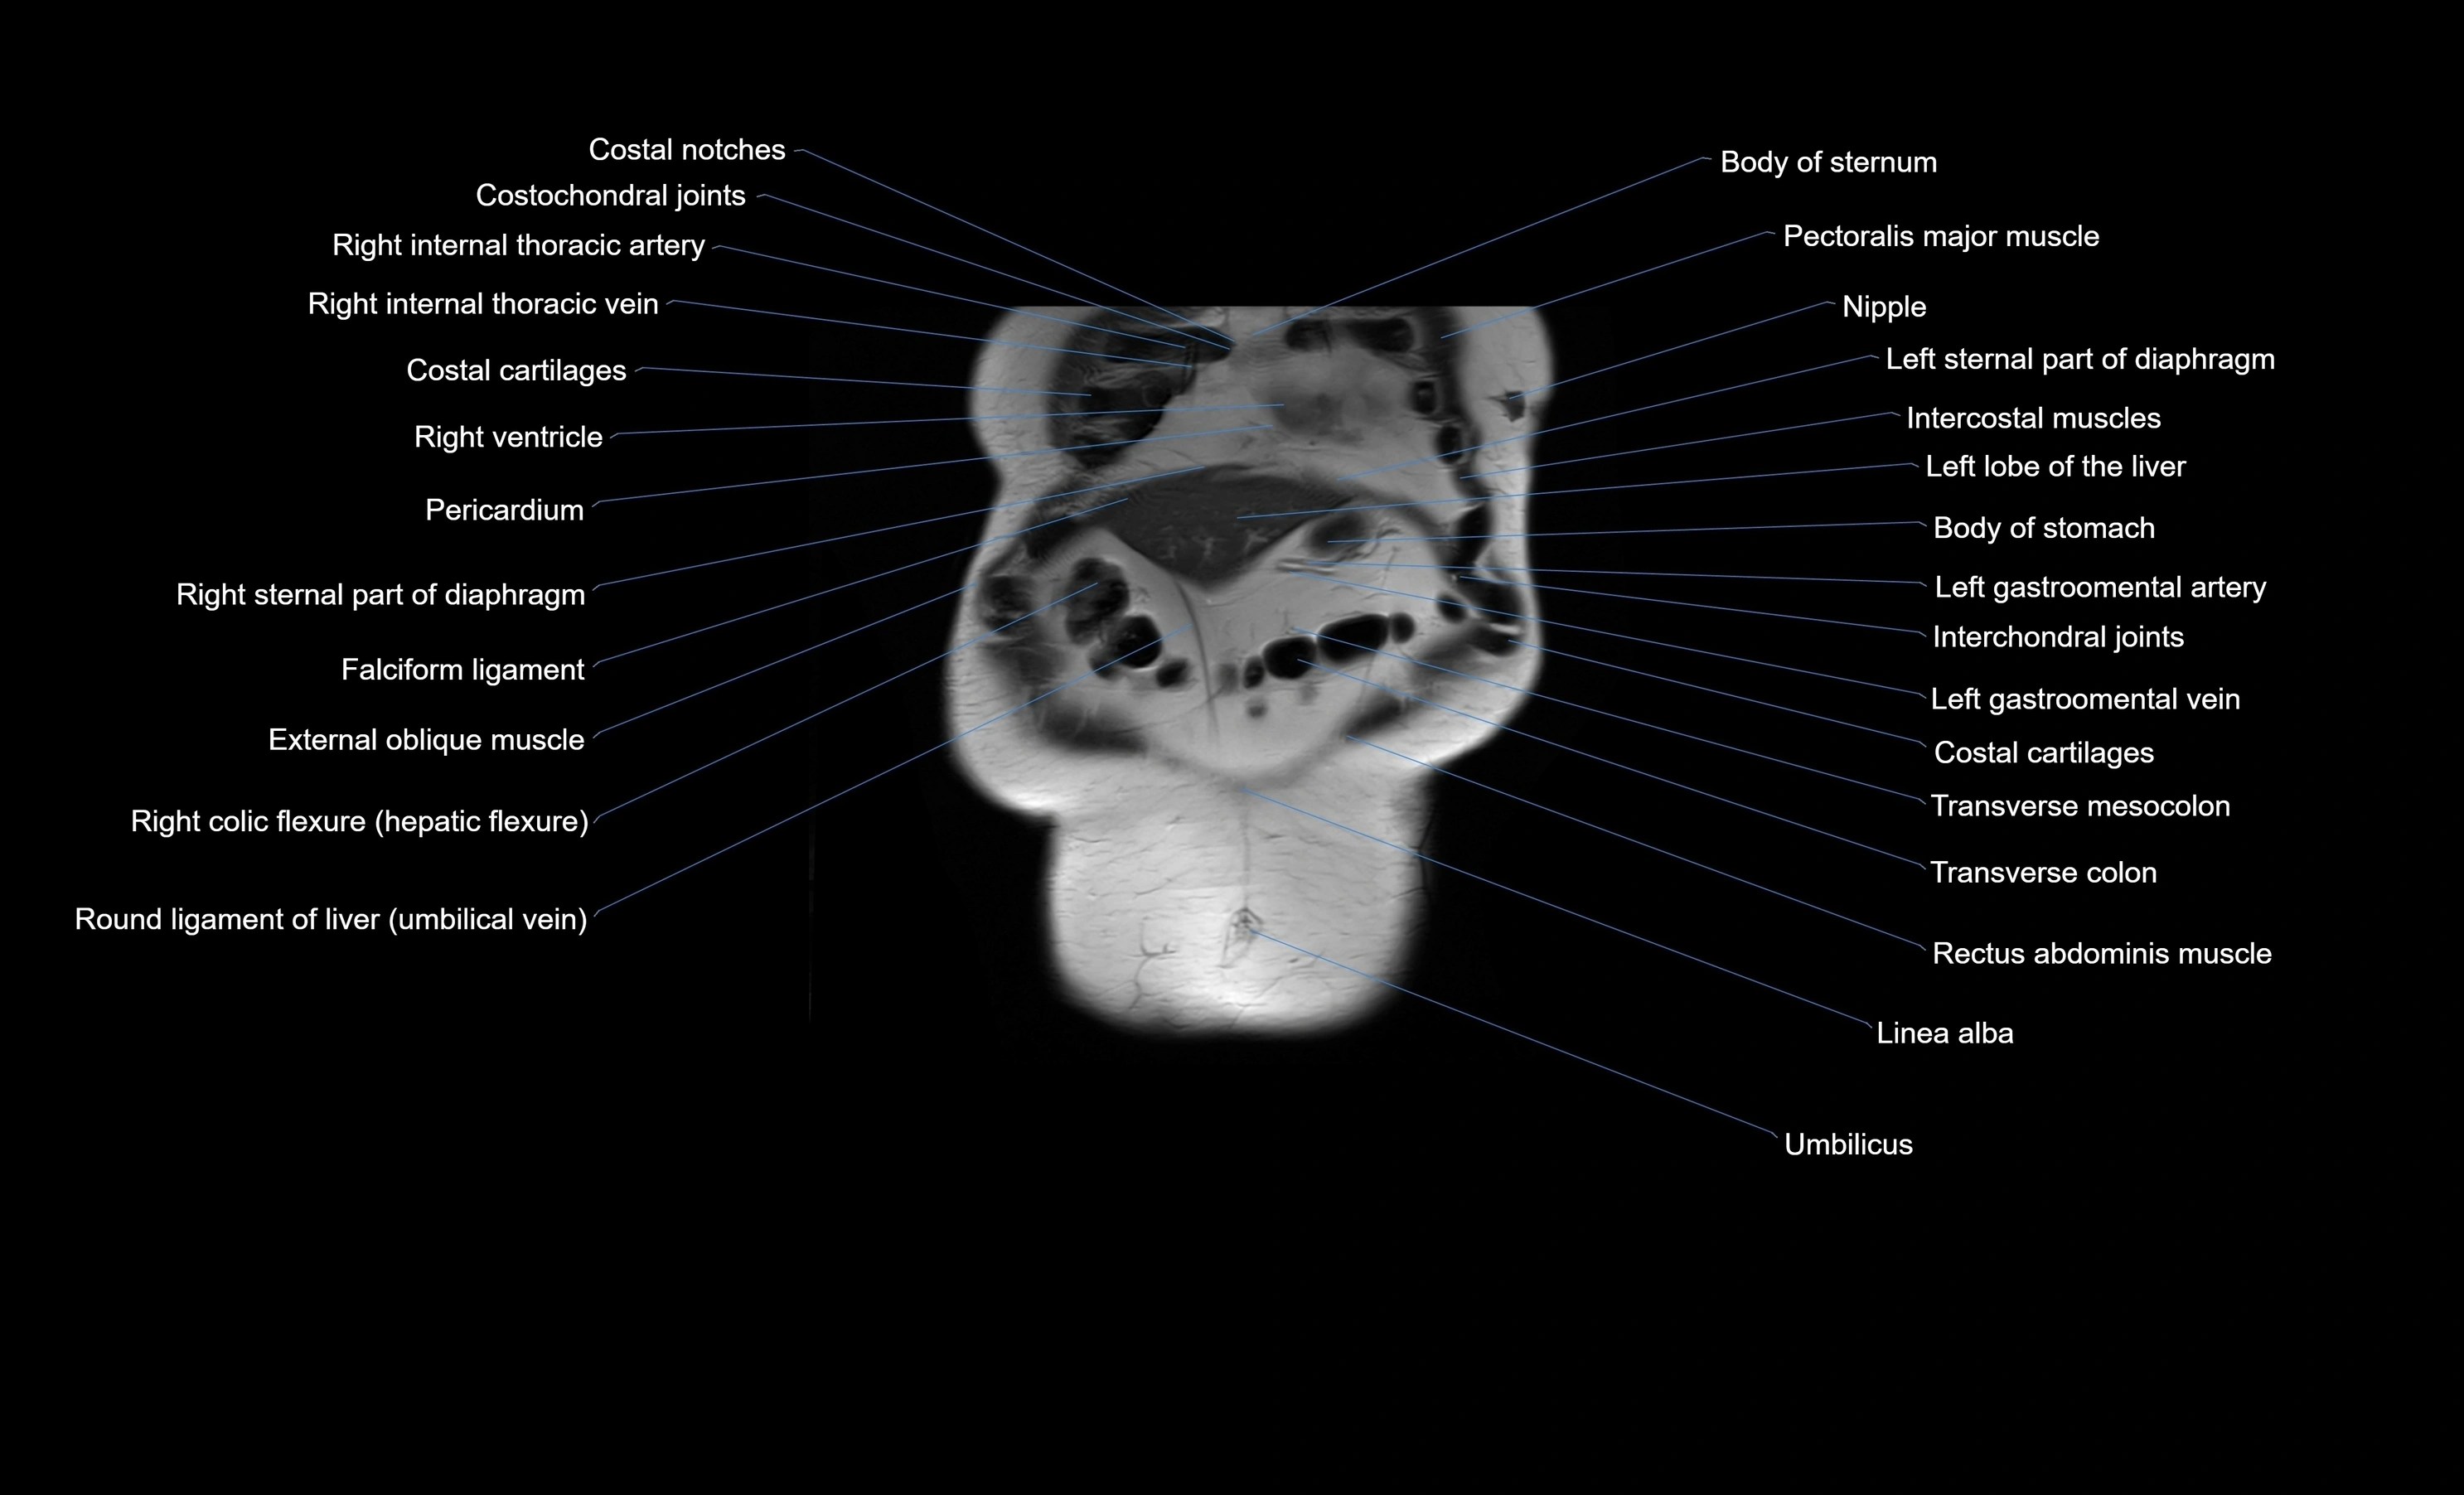

- Costochondral joints

- Intercostal muscles

- Pericardium

- Falciform ligament (liver)

- Right colic flexure (hepatic flexure)

- Ligamentum teres (round ligament of the liver)

- Linea alba

- Rectus abdominis muscle

- Transverse colon

- Transverse mesocolon